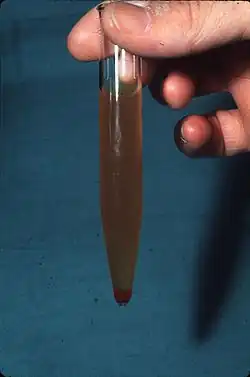

Транспортировка мочи должна производиться только при положительной (плюсовой) температуре окружающей среды, в противном случае выпадающие в осадок соли могут быть интерпретированы как проявление почечной патологии либо совершенно затруднят процесс исследования. В случае, когда на исследование доставлена «перемороженная моча», анализ придётся собрать повторно.